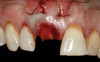

(21.) Postoperative periapical radiograph taken immediately after placement of the implant at site No. 8 demonstrating implant positioning centered with the planned location of the gingival zenith and two titanium alloy tacks that were used to stabilize the resorbable membrane apically.

Figure 21

Prior to the initiation of the surgery, the surgical guide was tried in to confirm proper seating and stability (Figure 15). A flapless approach was not considered because the need for further bone grafting at the time of implant placement had been anticipated through the digital planning. A slightly palatal crestal incision was made, followed by two vertical incisions on the mesial and distal aspects of the edentulous site in order to preserve the papilla and avoid additional esthetic compromise to the anterior sextant. Next, a full-thickness flap was elevated to facilitate removal of the tenting screw and permit visualization of the buccal plate (Figure 16). A standard guided protocol was followed to place the implant, and its final position mirrored that of the digital plan. As predicted, the prosthetically driven implant position resulted in an insufficient buccal plate (Figure 17); therefore, additional guided bone regeneration was performed to reinforce the area and prevent future breakdown (Figure 18 and Figure 19). Making periosteal incisions could have compromised the blood supply to the flap, so instead, it was stretched in order to achieve tension free coronal advancement.31The flap was secured utilizing horizontal mattress sutures with additional supportive interrupted sutures to ensure primary closure (Figure 20). An immediate postoperative periapical radiograph (Figure 21) and CBCT scan (Figure 22) were taken, demonstrating a final implant position centered with the planned location of the gingival zenith.